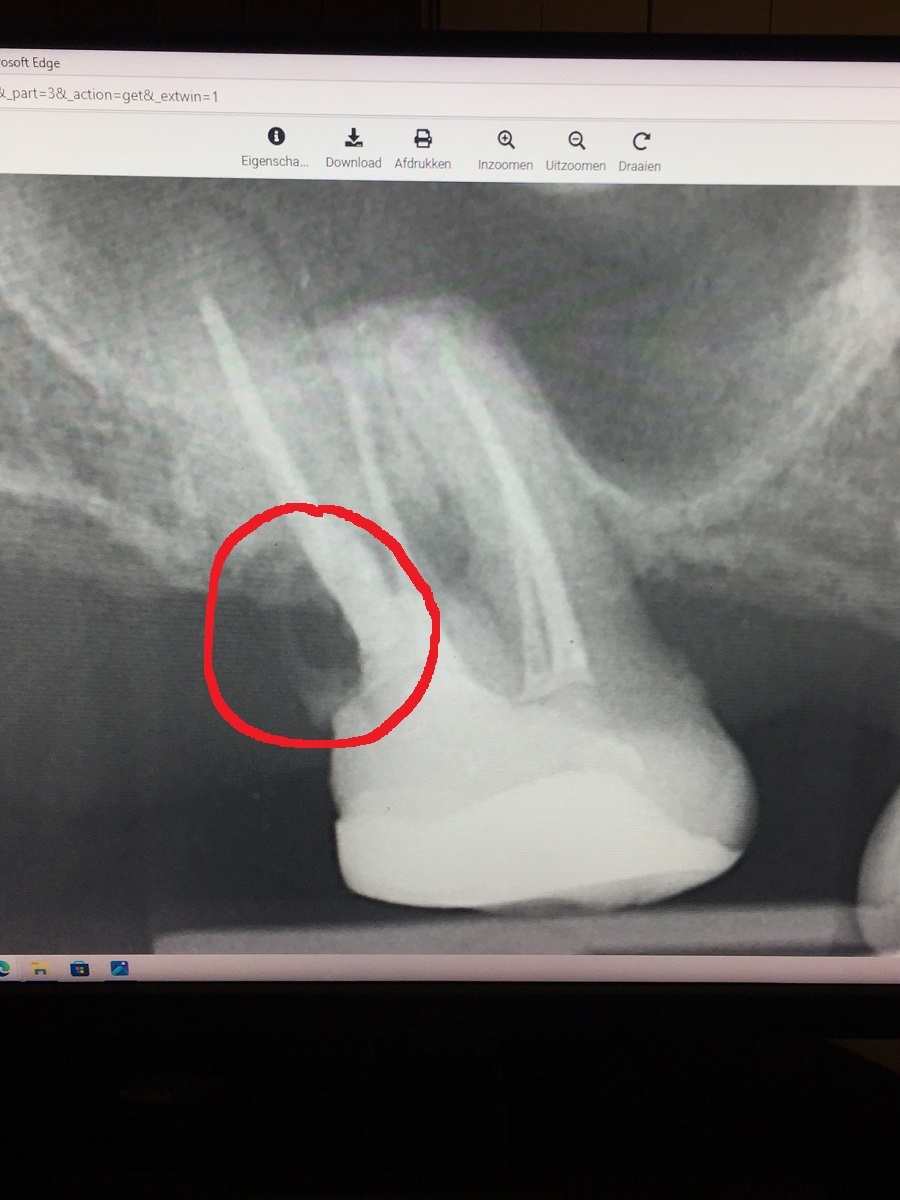

afijn vanmiddag naar de tandarts geweest en op de foto zag de tandarts ineens dan mijn wortel was opgelost. ze voelde ook met een haakje en had daar aan de achterkant wel wat diepe pockets. ze dacht aan een breuk in de wortel maar ik heb geen last met kauwen erop. alleen als ik met mijn tong op het kaakbot achter de kies druk dan voel ik wat. .

ik heb even een foto erbij voor Tandarts Richard .wat kunt u concluderen aan de hand van deze foto?

Tandarts_Richa…

idd lijkt op wortel resorptie. Element is helaas verloren. Oppassen voor mogelijke Antrum perforatie ( verbinding met neusholte) met verwijderen aangezien bot erg dun lijkt. Weet niet hoe de rest v h gebit eruit ziet.. maar nadenken over vervanging.

tingobop

Ik heb dan ook nog een vraag over de kies 17 waar ik de foto van gepost heb. ik snap de foto zelf niet zo goed. kunt u mij eens uitleggen wat er precies te zien is? voor zover ik kan zien is er een flink stuk van de wortel weg waar het gebied zwart is en niet grijs. maar het wortelkanaal waar de vulling zit staat er nog gewoon. hoe kan dit gezien alles er rond heen weg is?

gezien hoe goed ik er nog op kan kauwen kan ik mij eigenlijk niet voorstellen dat het stuk van de wortel wat niet meer word weergegeven op de foto er niet meer zou zijn maar alles is mogelijk natuurlijk.

ik ben vroeger eens bij een inval tandarts geweest en die vertelde dat je een wortel kon laten polijsten .hij vermoedde toen dat er mogelijk een ontsteking kon zijn waar de perforatie zat en was gedicht met MTA. omdat hier bacteriën aan de buitenkant konden verblijven. het heeft ook zeker 2 weken geduurd voordat de endodontoloog de kies ging behandelen en het gat heeft gedicht nadat de wortel door de tandarts geperforeerd was.

eigenlijk had de tandarts dit gat al gelijk moeten dichten maar die had geen microscoop en wilde de kies niet meer aanraken. ik zie wel op de foto waar de wortel onderbroken is precies zit waar de kies in het verleden is geperforeerd. zie andere foto van direct na de endo 10 jaar geleden.